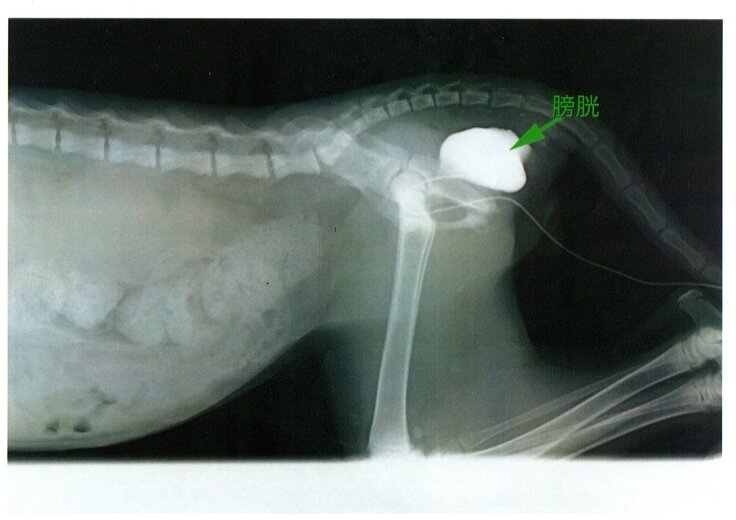

下の写真は横から見たレントゲンです。

白く写ってる部分(造影剤にて撮影)がずれてしまった膀胱になります。

本来なら、後脚左側腹部に位置しますが、衝撃によって移動してしまっています。

そのため、困難になってしまった排泄障害の治療のため手術を行いました。